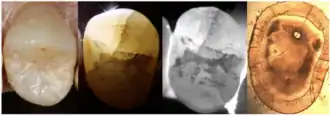

Enamel Fracture

4. Transillumination

Transillumination involves using fiber-optic light to illuminate the tooth surface, with light diffraction at the crack helping to locate it (Chanchala HP et al., 2022).

Microscopic Detection

5. Microscope detection

Cracks with width less than 18 μm are difficult to detect with the naked eye, making dental microscopes an essential tool for crack identification.

7. Radiographic examination

a. Periapical Radiographs

These provide detailed 2D images of the tooth and can detect fractures extending into dentin but may miss subtle enamel-only cracks due to their limited resolution.

b. CBCT

CBCT offers 3D imaging with high spatial accuracy, ideal for locating and assessing fractures extending into dentin or adjacent structures.

c. Micro CT

MicroCT has a high detection accuracy, capable of identifying cracks with widths ranging from a few tenths to tens of microns. It is widely regarded as the gold standard for detecting cracks in research on cracked teeth.